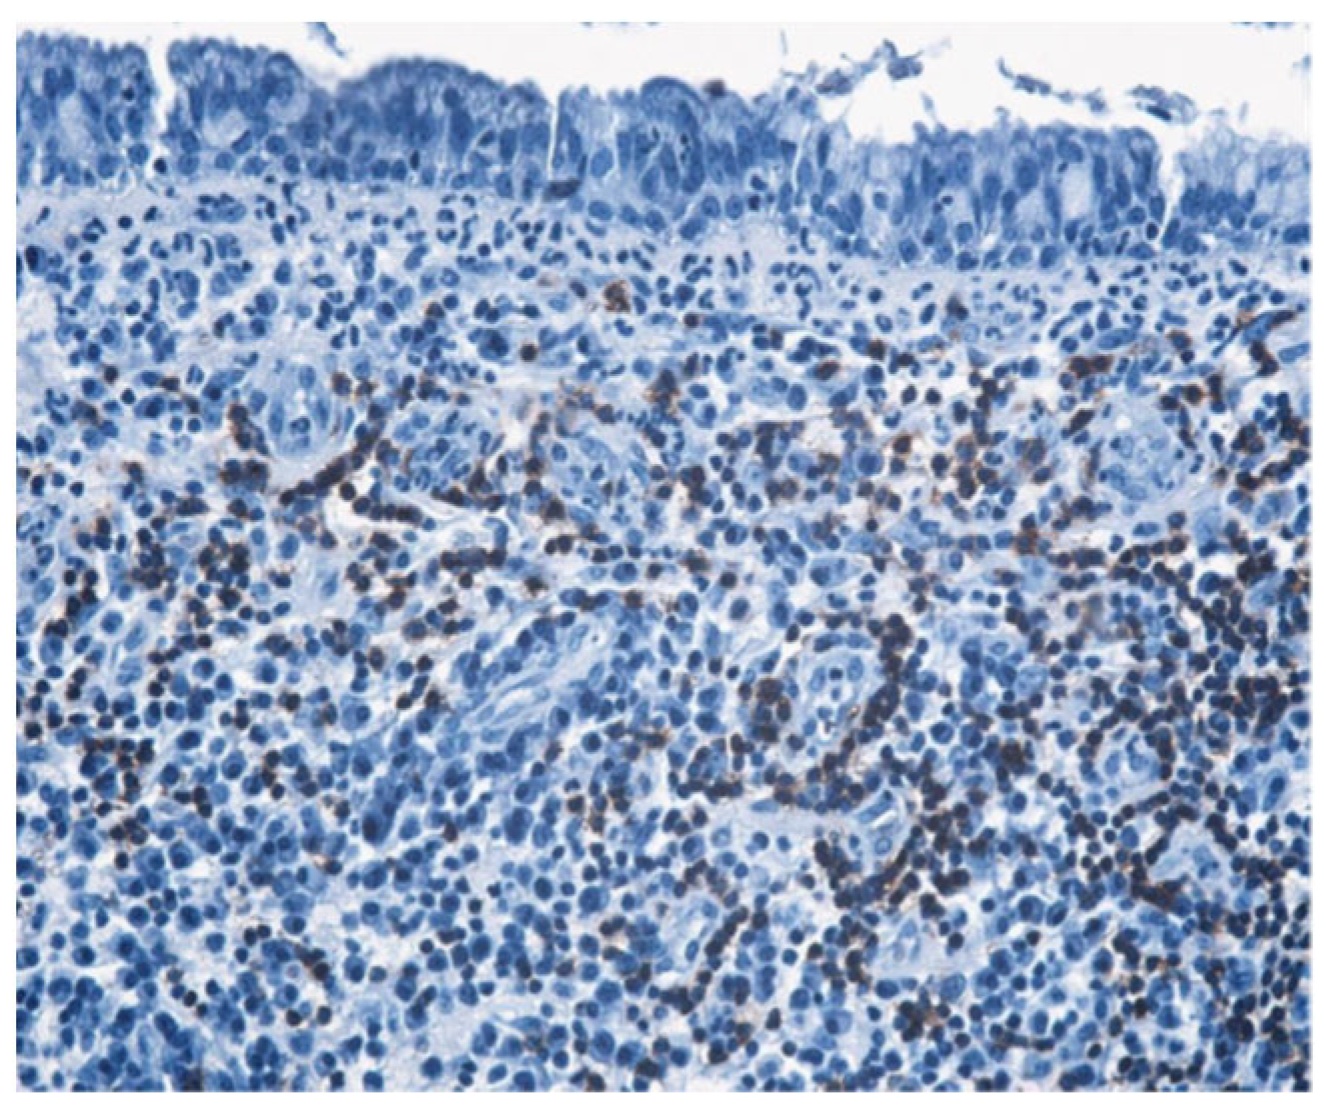

| Histopathologic Aspects | Number of Patients |

|---|---|

| Cholesteatom | 276 |

| Polip | 180 |

| Tympanic membrane mucosa chamber, epithelium with apocrine-like cells, and chronic inflammatory infiltrate | 128 |

| Cell Types | Percentage |

| Lymphocytes T | 42.55% |

| Lymphocytes B | 31.45% |

| Macrophages | 26.00% |